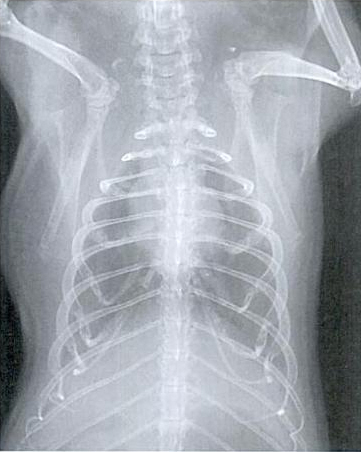

Slike dišnih puteva bez oboljenja:

Nedostatak tipičnih simptoma često otežava ranu dijagnozu. U slučaju bolesti se provode kliničke pretrage kao slušanje, mjerenje temperature, pulsa i promatranje frekvencije disanja. RTG pregled je koristan u slučaju dileme. Može pokazati da li i u kojem obimu postoje sjene u predjelu pluća. Kako se uzročnik ne može razlikovati, trebalo bi dati sekret iz nosa ili očiju, ili bris grla tj. nosa na pretrage kako bi se ustanovila kultura uzročnika i napravi antibiogram. U slučaju smrti, naročito ako je više životinja zaraženo, obdukcija bi imala smisla.